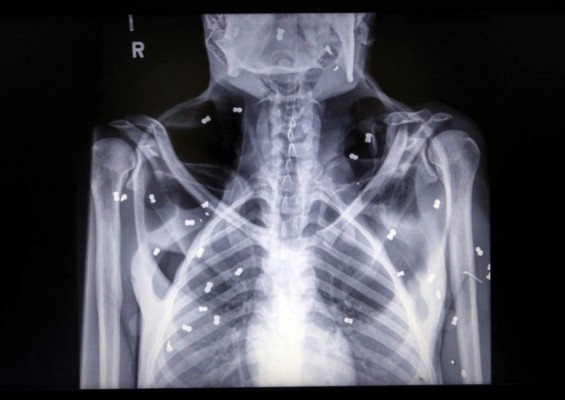

Foto de la radiografÍa de 'Hope' en donde se le ven los disparos.

Una orangutana fue encontrada con 74 disparos de perdigón en el cuerpo junto a su cría, que murió horas después por malnutrición, en la provincia indonesia de Aceh, anunció hoy el Ministerio de Medioambiente.

'La madre presentaba heridas en la mano derecha, la pierna derecha y la espalda, mientras que el bebé de un mes de edad presentaba síntomas de malnutrición', dijo el ministerio de Medioambiente en las redes sociales.

La hembra adulta, de unos 30 años y que recibió el nombre de Hope (esperanza), pudo ser salvada por los veterinarios aunque se encuentra en cuidados intensivos y sigue grave, mientras que la cría pereció y fue enterrada en el jardín del centro de cuarentena.